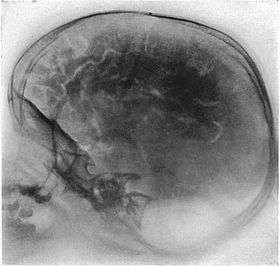

Pneumoencephalography (sometimes abbreviated PEG; also referred to as an "air study") was a common medical procedure in which most of the cerebrospinal fluid (CSF) was drained from around the brain by means of a lumbar puncture and replaced with air, oxygen, or helium to allow the structure of the brain to show up more clearly on an X-ray image. It was derived from ventriculography, an earlier and more primitive method where the air is injected through holes drilled in the skull.

Pneumoencephalography makes use of plain X-ray images. Unfortunately, these are very poor at resolving soft tissues, such as the brain. Moreover, all the structures captured in the image are superimposed on top of each other, which makes it difficult to pick out individual items of interest (unlike modern scanners which are able to produce fine virtual slices of the body, including of soft tissues). Therefore, pneumoencephalography did not usually image abnormalities directly, rather their secondary effects. The overall structure of the brain contains crevices and cavities which are filled by the CSF. Unfortunately, both the brain and the CSF produce similar signals on an X-ray image. However, draining the CSF allows for greater contrast between the brain matter and the (now drained) crevices in and around it, which then show up as dark shadows on the X-ray image. The aim of pneumoencephalography is to outline these shadow-forming air-filled structures so that their shape and anatomical location can be examined. Following the procedure, an experienced radiologist reviews the X-ray films to see if the shape or location of these structures have been distorted or shifted by the presence of certain kinds of lesions. Unfortunately, this also means that in order to show up on the images, lesions have to either be located right on the edge of the structures or if located elsewhere in the brain, be large enough to push on surrounding healthy tissues to an extent necessary to cause a distortion in the shape of the more distant air-filled cavities (and hence distal tumors detected this way tended to be fairly large).